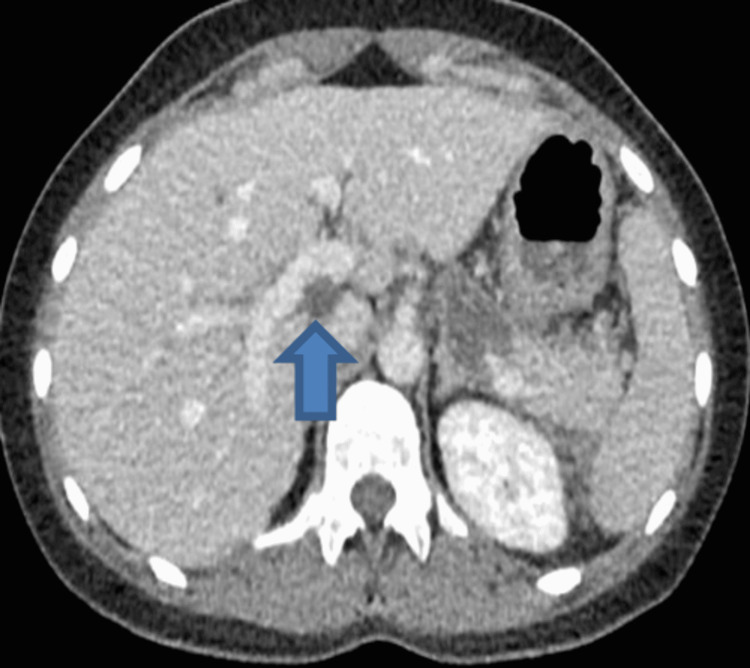

Computerized tomography scan of abdomen and pelvis showed features of acute pancreatitis without any evidence of pancreatic necrosis and thin-walled distended gallbladder containing multiple gallstones. The distal CBD was dilated measuring up to 13 mm with positive double duct sign (moderate intra- and extra-hepatic duct dilatation and mild pancreatic duct dilatation) as shown in Figures 1–3.